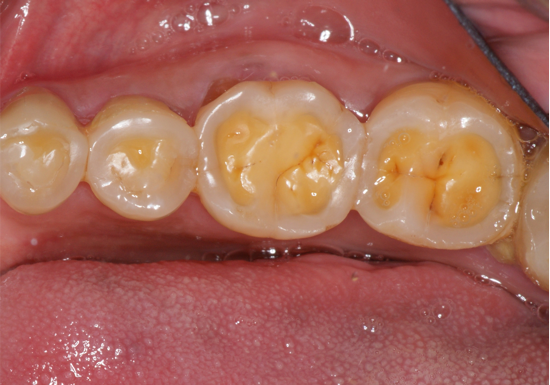

Concavities on the lingual surfaces of maxillary incisors (Figure 5) or occlusal surfaces of premolars and molars (Figure 6) with hollowed areas are signs of dental erosion that may be combined with attrition. Gastric acid is the most common cause of erosion on the lingual aspects of teeth. The most frequent etiology of gastric acid attack is the clinical diagnosis of GERD.13 Patients with anorexia nervosa and bulimia nervosa exhibit higher incidences of dental erosion.29 In Figure 7, a schematic drawing of an upper incisor demonstrates the sequence of loss of dentin and enamel on the lingual/palatal aspect. The direct contact of acid on the tooth structure is the main mechanism as the inorganic material dissolves, leading to a loss of surface hardness.13

Fig 6. Eroded and worn occlusal surfaces with hollowed out areas.

Figure 6